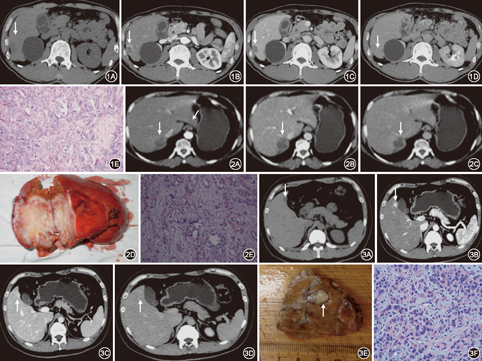

(1)CT平扫:呈低密度的15例,呈高低混杂密度的4例,呈等密度的1例。(2)动态CT增强示:病灶周边薄环强化型6例,病灶周边厚环强化型7例,全瘤灶无强化型1例,病灶内岛状强化或不均匀强化5例,全瘤灶明显强化型1例。

(1)呈低密度的15例,其中8例是中分化腺癌,以纤维组织为主,周围有成活的肿瘤组织4例;以纤维、坏死组织混杂,周围有成活或中心部分有成活的肿瘤组织4例;6例是中分化腺癌为主,部分低分化,都以纤维、坏死组织不呈比例混杂,病灶周围有成活或中心不规则分布有成活的肿瘤组织;1例是低分化腺癌,肿瘤内呈大量肿瘤组织为主,癌巢之间为少量纤维结缔组织,无坏死组织。(2)呈高低混杂密度的4例,其中3例是中分化腺癌,肿瘤内呈大量坏死组织为主,血管分布稀少,坏死组织内有少量纤维结缔组和(或)肿瘤组织;1例是中分化腺癌为主,部分高分化,肿瘤内呈大量坏死组织为主,坏死组织内及周围有肿瘤组织及少量纤维结缔组织。(3)稍高密度的1例,高分化腺癌,肿瘤内呈大量坏死组织内、纤维结缔组,周围见肿瘤组织。

(1)病灶周边薄环强化型6例,其中5例有延迟强化,肿瘤边缘薄层完整或不完整的中度环形强化影对应的是成活的肿瘤组织;部分无强化坏死区边缘病例同时见锥形或短条形强化影从边缘向肿瘤内部延伸对应的也是成活的肿瘤组织;肿瘤内部其他为轻度不定形强化的对应的是纤维组织(图1)。(2)病灶周边厚环强化型7例,其中4例有延迟强化,动脉期肿瘤边缘呈完整或不完整的厚环状强化、肿瘤内部大部分不定形强化对应的是成活的肿瘤组织,中心不强化的为坏死组织为主,间杂着少量纤维组织,其中1例肿瘤内部为大量纤维组织为主,3期扫描强化不明显,病理上为硬化型胆管细胞癌(图2)。(3)全瘤灶无强化型1例,3期扫描肿瘤均无强化,对应的病理是肿瘤明显囊性扩张,显著出血、坏死,肿瘤与正常肝组织间见成活肿瘤细胞。(4)病灶内岛状强化或不均匀强化5例,肿瘤内呈大量坏死组织为主,血管分布稀少,病灶内岛状强化或不均匀强化为成活的肿瘤组织及少量纤维结缔组。(5)全瘤灶明显强化型1例,有轻度延迟强化,对应的病理是:癌细胞小-中等大,大小一致,见不规则巢团状,可见线状或腺管状排列,未见坏死(图3)。